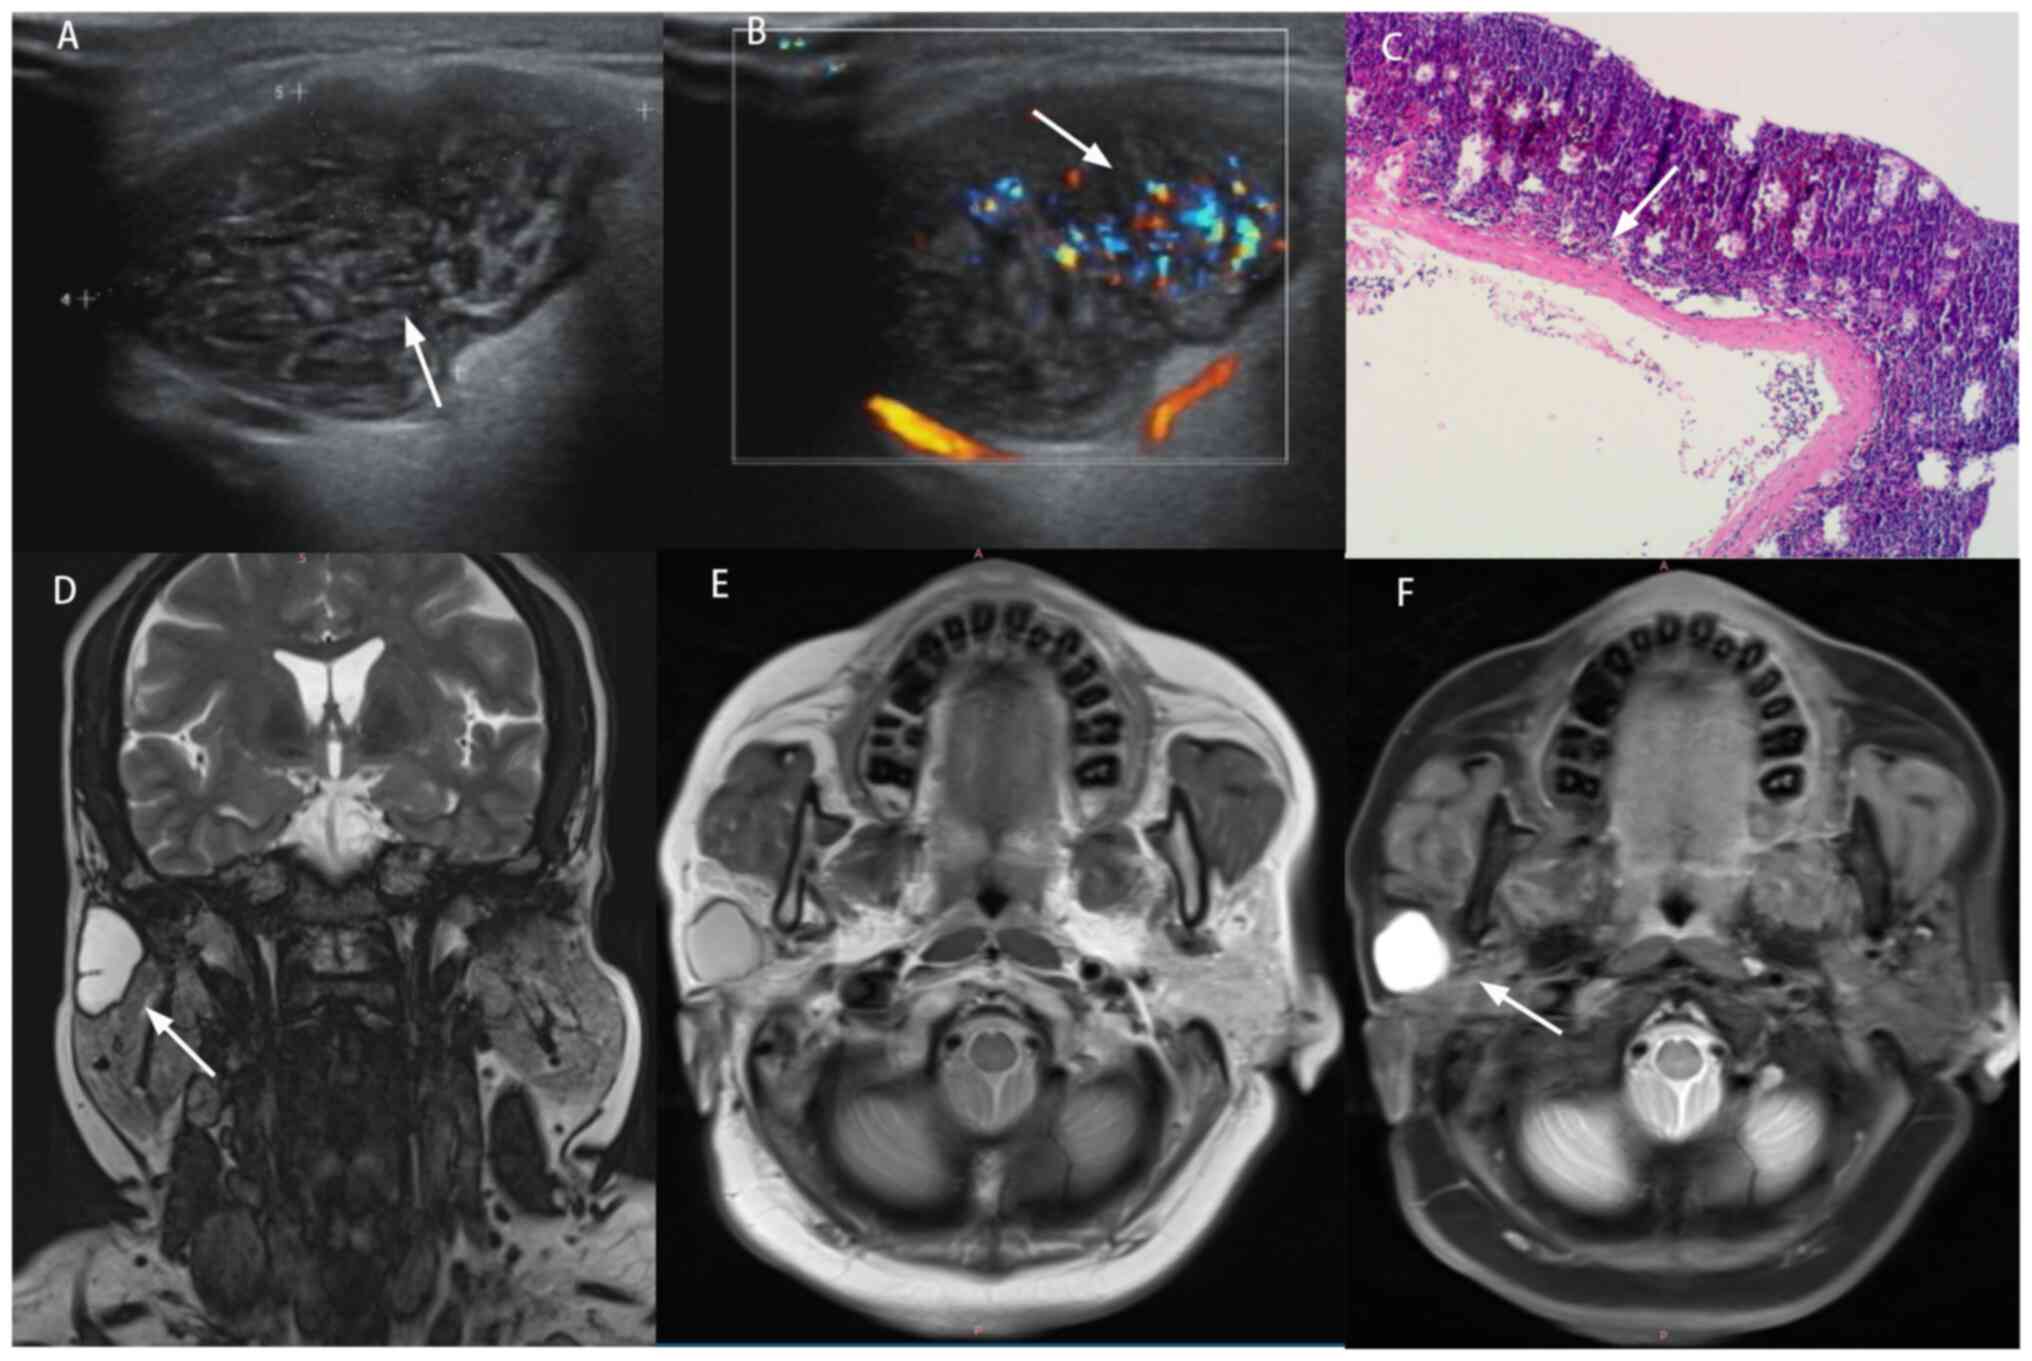

Features of a cyst on US, MRI and

histopathology. (A) US: Irregular shape, well-defined margins,

marked hypoechogenicity and moderate heterogeneity (arrow). (B)

Color Doppler: Prominent intralesional vascularity (arrow). (C)

Histopathology (H&E stain): Keratinizing stratified squamous

epithelial lining with luminal necrotic debris (arrow). (D)

T2-weighted MRI: Well-circumscribed cystic lesion with homogeneous

hyperintensity (arrow). (E) T1-weighted MRI: Entirely homogeneous

hyperintensity (no hypointense foci). (F) Short Tau Inversion

Recovery sequence: No solid enhancement (arrow) or enlarged lymph

nodes. US, ultrasound.

Figure 5

Features of a cyst on US, MRI and histopathology. (A) US: Irregular shape, well-defined margins, marked hypoechogenicity and moderate heterogeneity (arrow). (B) Color Doppler: Prominent intralesional vascularity (arrow). (C) Histopathology (H&E stain): Keratinizing stratified squamous epithelial lining with luminal necrotic debris (arrow). (D) T2-weighted MRI: Well-circumscribed cystic lesion with homogeneous hyperintensity (arrow). (E) T1-weighted MRI: Entirely homogeneous hyperintensity (no hypointense foci). (F) Short Tau Inversion Recovery sequence: No solid enhancement (arrow) or enlarged lymph nodes. US, ultrasound.